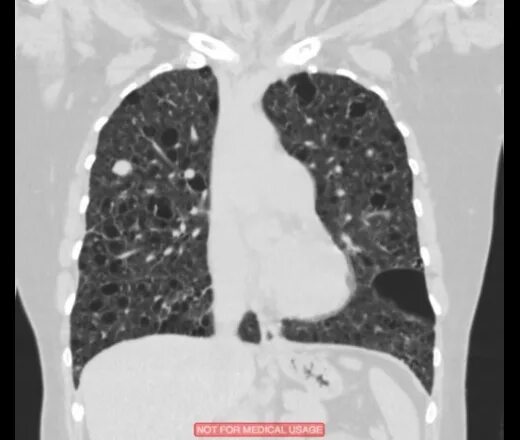

Линейный пневмофиброз